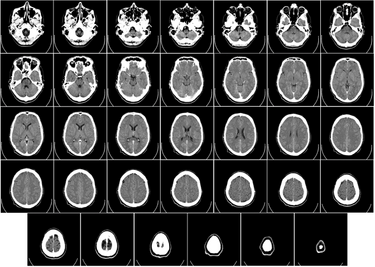

Computer Tomography, or CT, images are a form of x-ray scan which creates a 3D image of the scanned object. CT images are a compilation of computer processed x-ray images taken at a range of angles around the object to produce a single cross sectional image. Then the object is moved forward within the machine to scan the next cross section using the same technique. All of the cross sectional images can then either be viewed side by side or stacked on top of one another to create a 3 dimensional scan of the object.1 An example of a CT scan with the 2D images lined up next to one another can be seen to the left in Figure 1.

The first CT scanners developed had very low resolution with a resolution of 80 x 80 images and took about 5 minutes to take each scan at every angle, then an additional 2.5 hours to process the images into a single computer processed CT image .5 Modern day CT scanners have a resolution ranging from 1024 x 1024 to 2048 x 2048 and have the ability to take scans in less than a second, allowing from CT images of organs in motion, such as a beating heart.6 The improvement of over time of CT image resolution can be seen in Figure 2 to the right.